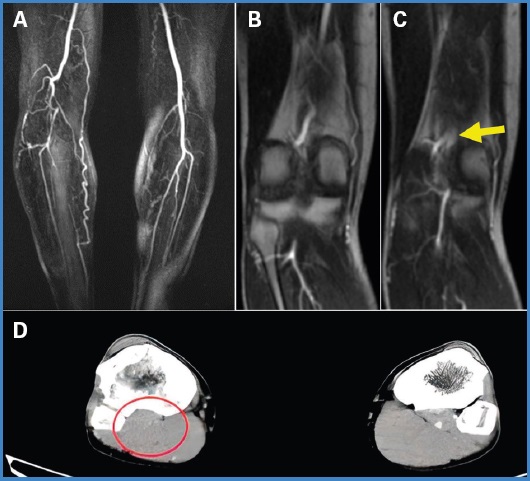

El estudio se complementa con angiorresonacia, que muestra una banda fibrosa que se extiende desde el paquete vascular al aspecto medial y posterior del fémur distal en relación con oclusión de 45 mm de la arteria poplítea derecha, con gastrocnemios de configuración normal, lo que define un atrapamiento de tipo III (Fig. 1). Adicionalmente se identifica rama colateral que emerge del sitio de la oclusión proximal, transcurre lateralmente y desemboca en el sitio de la reconstitución distal, con disminución del calibre del tronco tibioperoneo y tibial anterior respecto a la extremidad izquierda.

Figura 1. Angiorresonancia: A. Oclusión de la arteria poplítea derecha, ramas colaterales con reconstitución del flujo distal. B. Segmento de la arteria poplítea antes de la oclusión. C. Banda fibrosa que genera oclusión de la arteria. Angiotomografía: D. Corte axial. Oclusión de la segunda porción de la poplítea derecha.